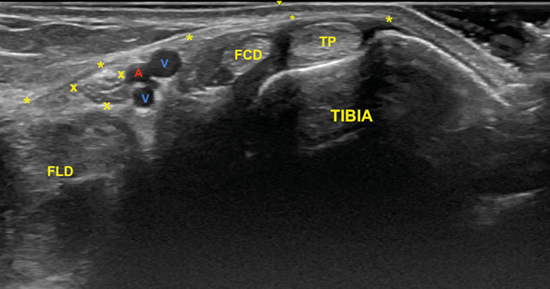

Para realizar la exploración sonográfica, se debe exponer la cara medial del tobillo y el pie. Se ha de comenzar con el examen del nervio tibial en eje corto (plano transverso), situando la sonda en el túnel tibiotalar superior (Figuras 4 y 5)5.

El nervio tibial, que se sitúa en superficie a las estructuras musculotendinosas y bajo la fascia crural, de forma habitual está dispuesto posterior a los vasos tibiales posteriores (Figura 6).

Figura 6. Túnel tibiocalcáneo. El examen en eje corto, bajo la fascia crural (*) y de anterior a posterior, muestra el tendón tibial posterior (TP), el tendón flexor largo de los dedos (FCD) aún con fibras musculares, y el músculo flexor largo del primer dedo (FLD). Entre estas dos estructuras se encuentra el haz neurovascular que está formado por las venas (V), la arteria (A) tibial posterior y por el nervio tibial (rodeado por X).